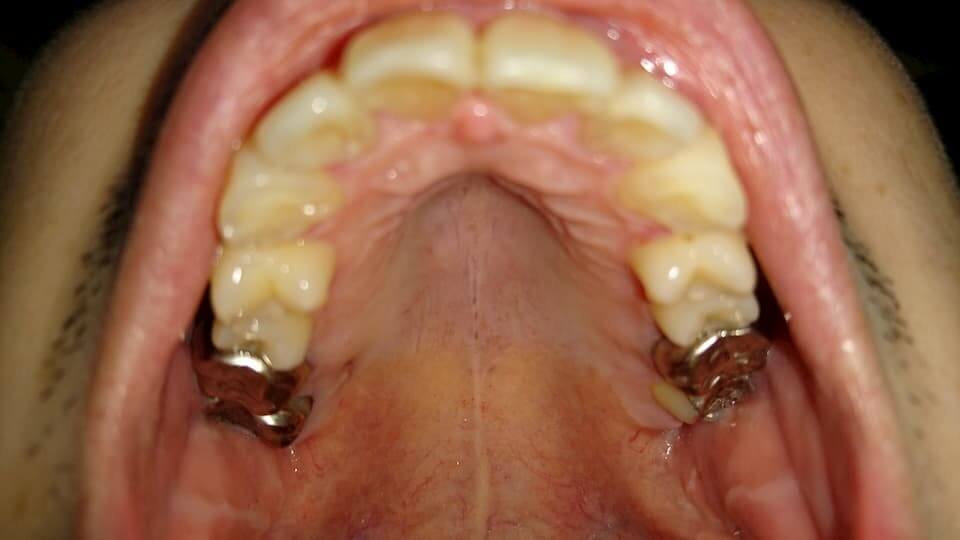

歯の写真